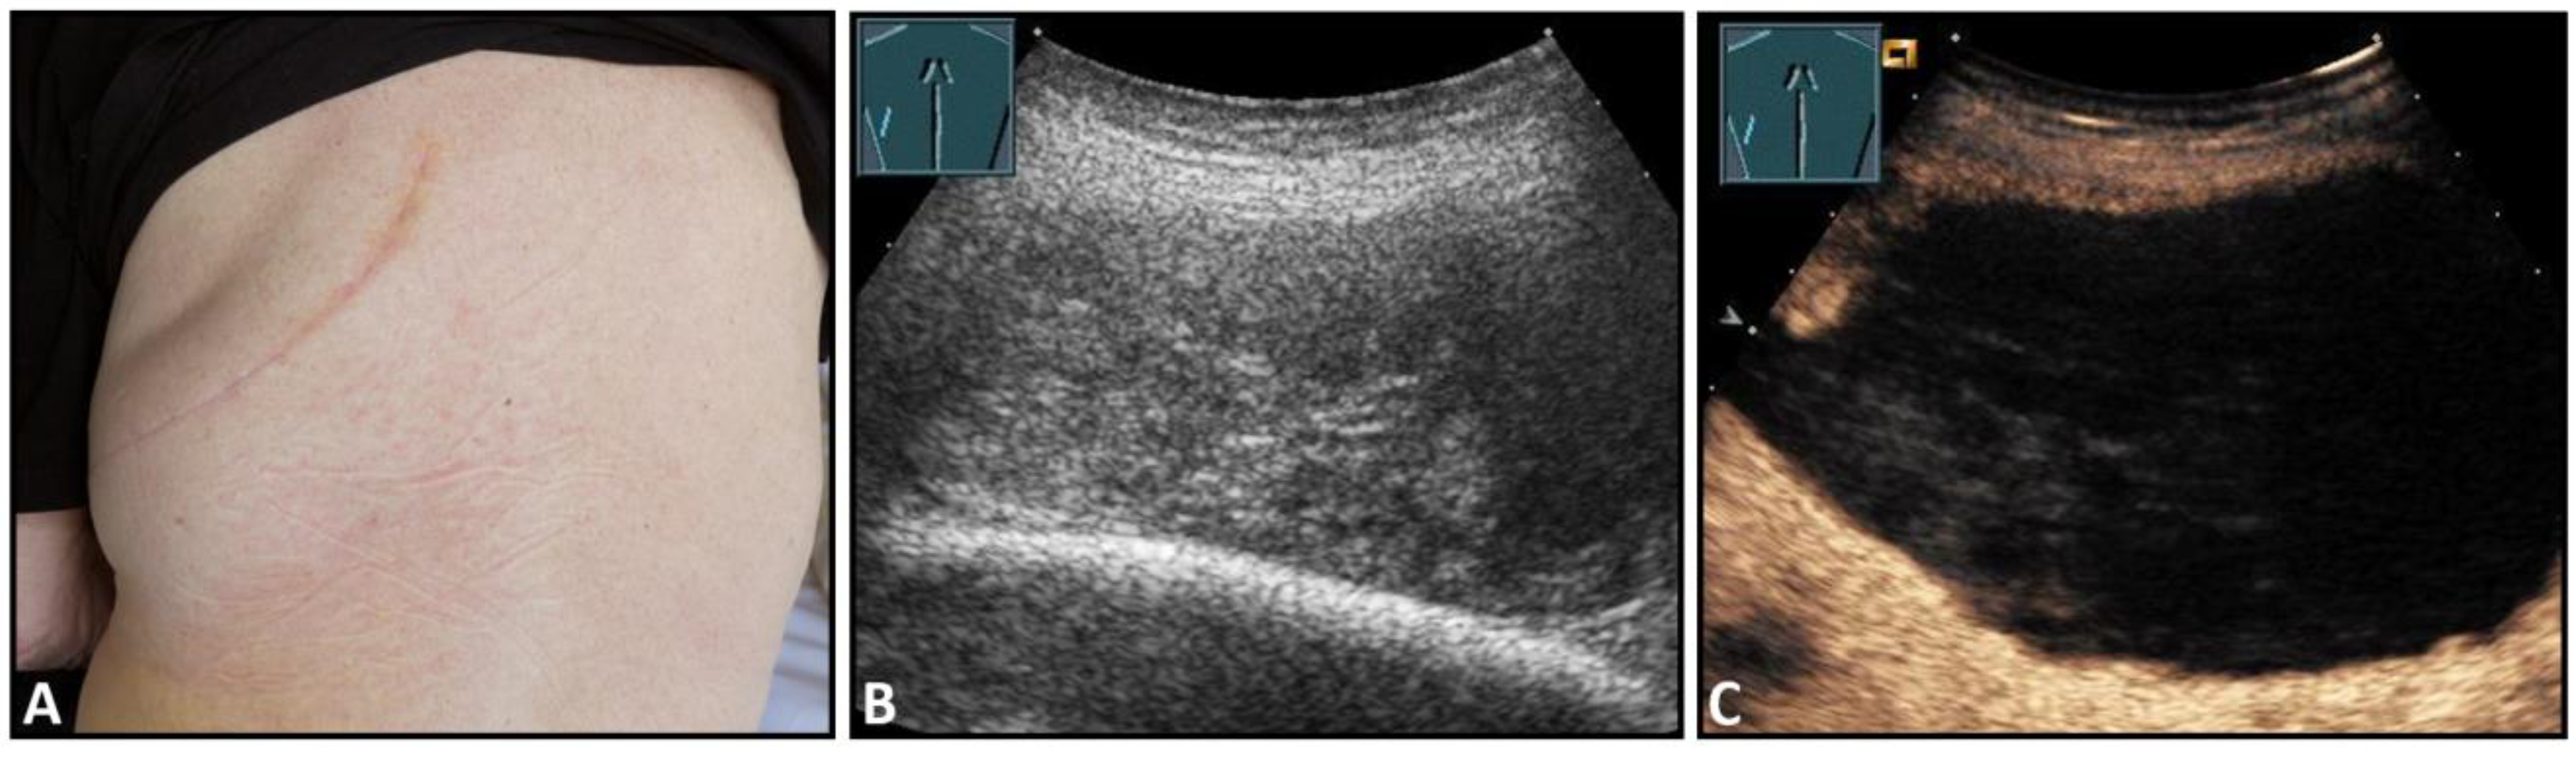

Hematomas of the chest wall are usually the result of blunt or penetrating trauma or arise after thoracic surgery. Spontaneous hematomas are found in rare cases in anticoagulated patients or in patients with coagulopathies and/or malignant tumors of the chest wall. The sonographic image depends mainly on the age or degree of organization of the hematoma. Whereas fresh hematomas are inhomogeneously hyperechoic due to their high erythrocyte content, organized hematomas are usually inhomogeneously hypoechoic or even nearly anechoic. CEUS is helpful in the differentiation of solid tumors (Figure 1).

Figure 1.

A patient after surgery for a bronchial carcinoma with a palpable chest wall tumor (A). B-mode US reveals a heterogeneous echogenic mass (B) without enhancement on CEUS (C), consistent with hematoma of the chest wall.